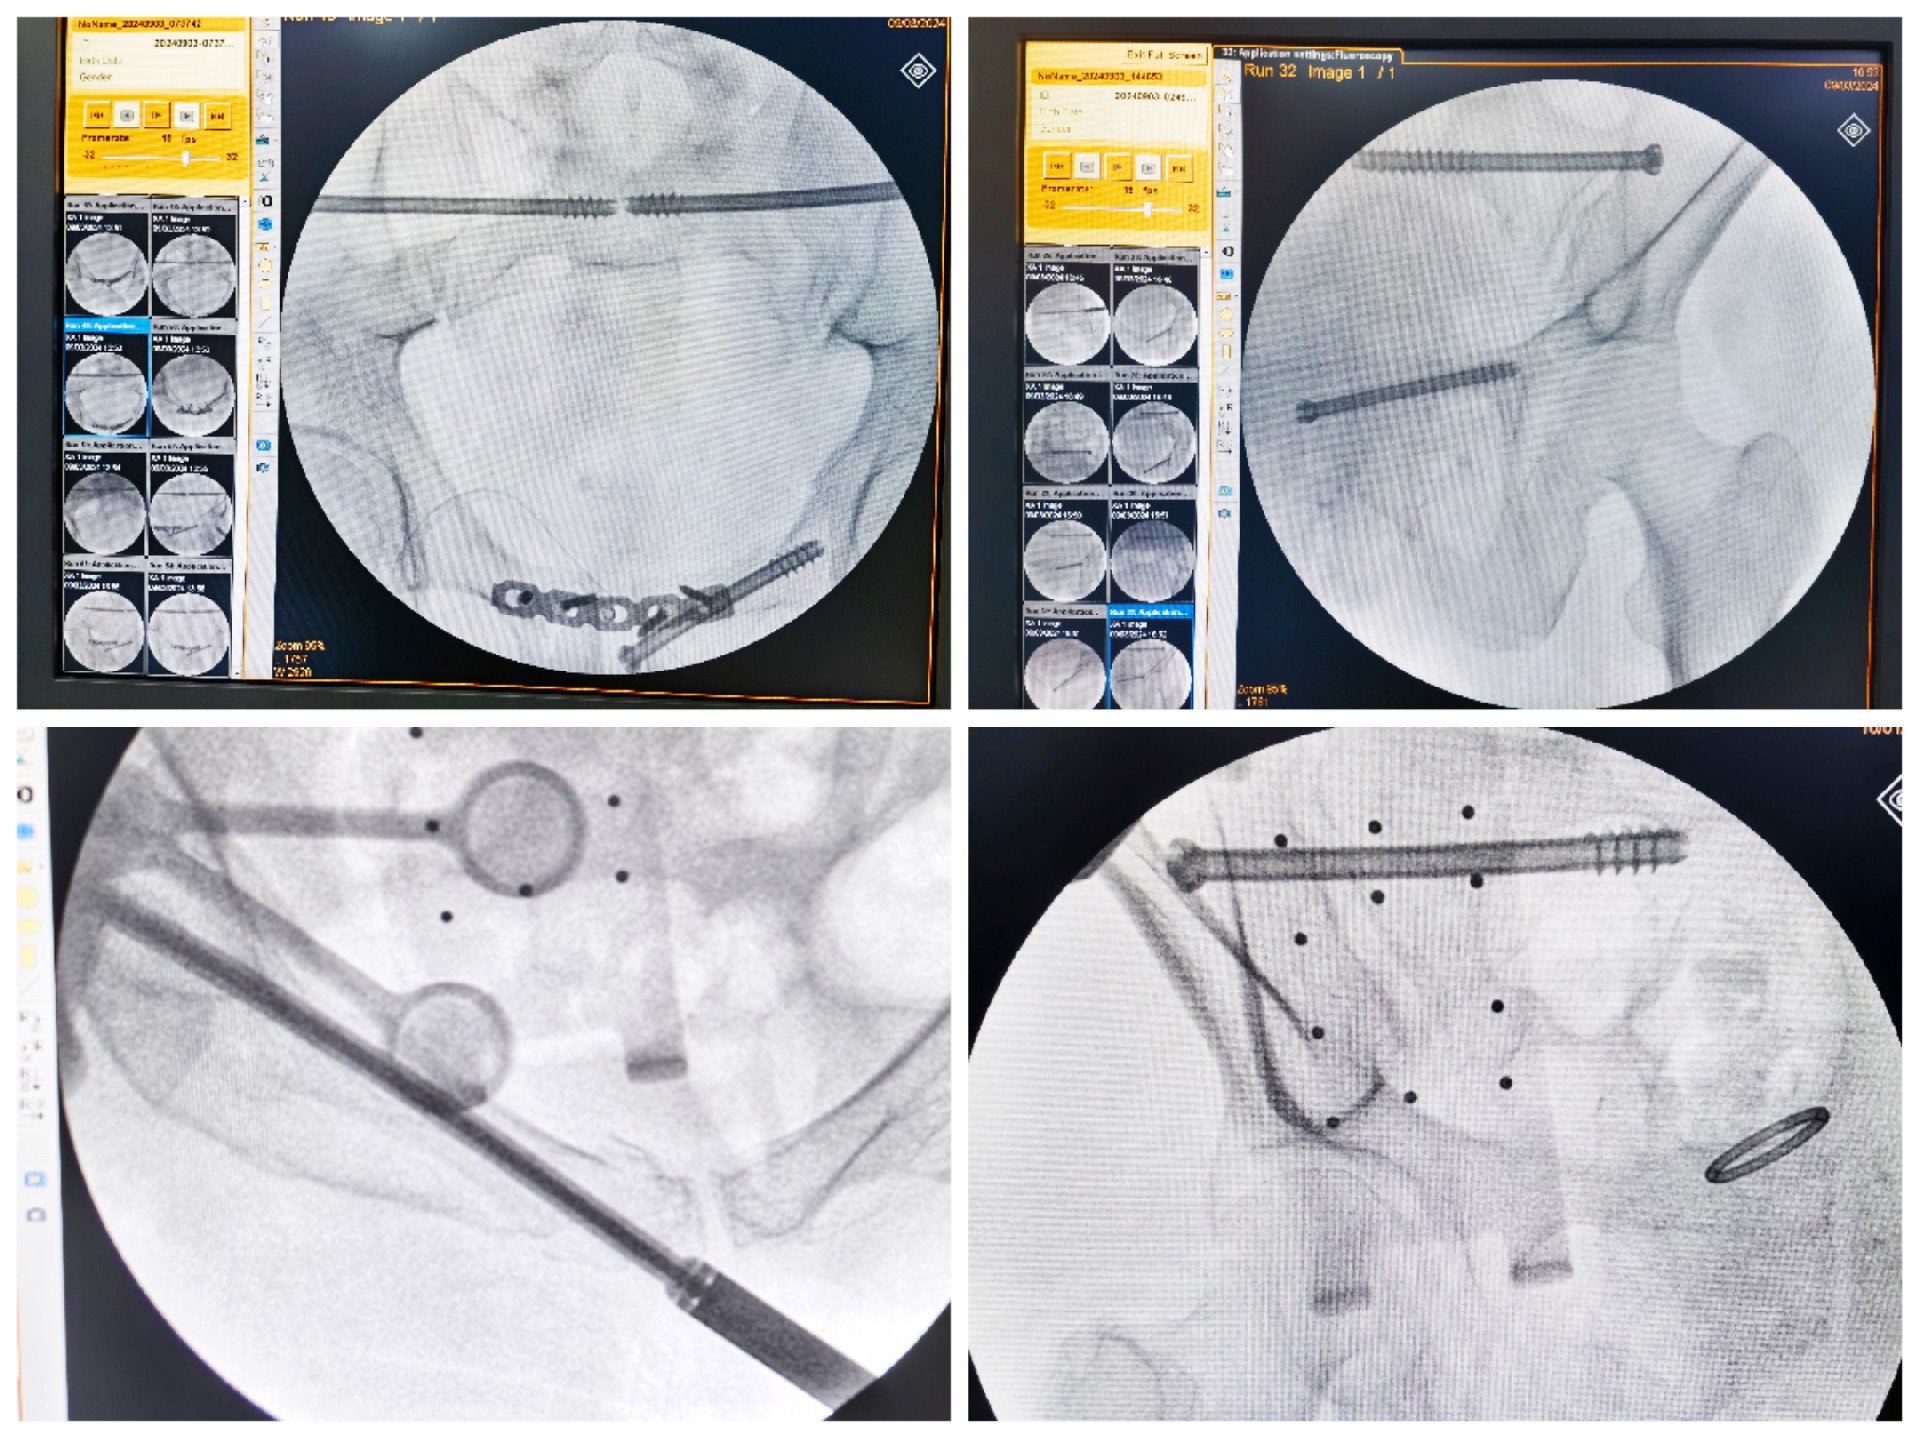

傳統(tǒng)的骨盆骨折微創(chuàng)手術(shù)中,骶髂螺釘?shù)嚷葆斨萌氲碾y點在于骨盆部位解剖十分復(fù)雜,螺釘置入如有偏差極易損傷重要神經(jīng)及血管,手術(shù)不僅依靠手術(shù)醫(yī)師豐富的經(jīng)驗,還需要術(shù)中反復(fù)的C型臂透視及調(diào)整,對患者及醫(yī)生都有較大輻射。而利用HoloSight知見創(chuàng)傷骨科機器人進行骨盆骨折微創(chuàng)手術(shù),通過高精度光學(xué)定位追蹤技術(shù)與混合現(xiàn)實技術(shù),使整個微創(chuàng)手術(shù)全程可視化,可以在電腦屏幕上實時顯示螺釘?shù)木珳?zhǔn)置入位置,降低手術(shù)風(fēng)險,提高手術(shù)效率及安全性。

術(shù)前,手術(shù)團隊認(rèn)真分析討論病例,全面掌握骨盆骨折微創(chuàng)治療的關(guān)鍵技術(shù),提前設(shè)計手術(shù)方案并反復(fù)模擬演練手術(shù)過程。術(shù)中,利用HoloSight知見創(chuàng)傷骨科機器人規(guī)劃骨折復(fù)位方案及定位螺釘通道,實現(xiàn)精準(zhǔn)微創(chuàng)手術(shù)。手術(shù)通過不足1cm小切口完成,最大程度地減少了術(shù)中出血,術(shù)中幾乎都是一次性成功精準(zhǔn)微創(chuàng)地置入內(nèi)固定螺釘,減少了醫(yī)源性操作對骨折周圍骨質(zhì)的影響,實現(xiàn)骨折微創(chuàng)固定的同時盡可能提高骨折固定的穩(wěn)定性,為術(shù)后患者的快速康復(fù)創(chuàng)造了有利條件。